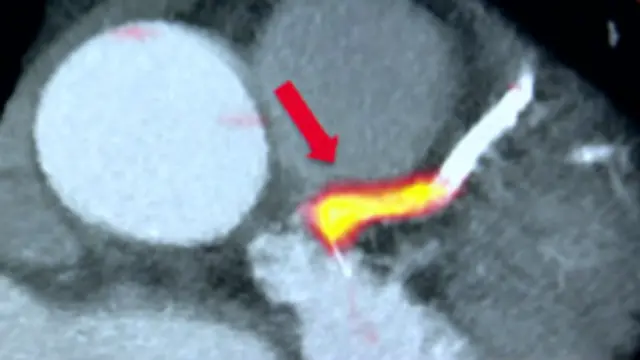

Дослідники використали радіоактивний маркер, який знаходить активні і небезпечні судинні нальоти. Це поєднують з зображеннями серця і судин у високій роздільній здатності.

У результаті отримують дуже детальну картину серця з чітко позначеними зонами небезпеки.

Скан дуже точно показав зону жирового нальоту, який викликав серцеві напади в 37 із них. Результати цих тестів оприлюднено в спеціалізованому медичному виданні <link type="page"><caption> Lancet</caption><url href="http://www.thelancet.com/journals/lancet/article/PIIS0140-6736(13)61754-7/abstract" platform="highweb"/></link>.